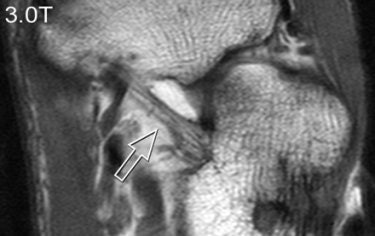

| A 31-year-old healthy male volunteer. Axial T1-weighted fast spin-echo images of foot show superior delineation of spring ligament (arrow) at 3 T (top and middle) as opposed to 1.5 T (below); 3.0TGR = 3.0T with GRAPPA algorithm. No significant difference was found between (top) and parallel (middle) acquisitions at 3 T; visualization of this ligament was rated very good at 3 T and as moderate at 1.5 T (below) by both radiologists. |

According to the results, GRAPPA MR resulted in a 44% reduction in scan time compared with conventional imaging. SNRs and CNRs doubled on the SPGR sequence at 3 tesla. These 3-tesla images also demonstrated comparable edge sharpness.

Image quality was rated highest on 3-tesla images. The axial T1-weighted sequence was given an average score of 3.4 at 3 tesla for parallel and normal acquisitions versus a score of 2.8 for 1.5 tesla. Visualization of ligaments and tendon abnormalities were also rated highly on parallel 3-tesla MR.